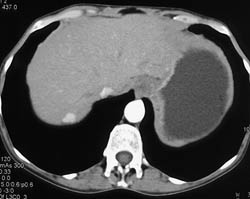

Budd-Chiari Syndrome